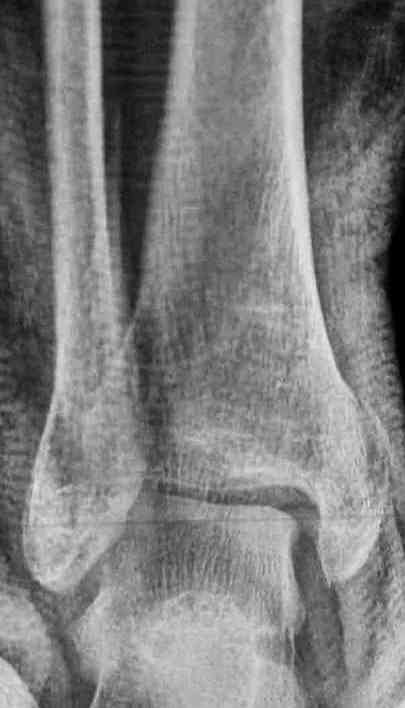

Уже 15 лет в отделении мы активно оперируем свежие переломы ГСС по принципам АО и вполне удовлетворены результатами лечения свежей травмы. В случаях же операций при позднем поступлении или реконструкции после неудачных вмешательств в ряде случаев сохраняется нестабильность ГСС, тенденция к вальгусной деформации. В свежих случаях никогда не приходилось производить шов дельтовидной связки, пластики тоже ни разу не выполнялись. Два примера на снимках.Первый - врач 38 лет, неудачно оперированный в своей больнице с двухлодыжечным переломом, разрывом МБС был повторно оперирован через 8 месяцев. Пытались восстановить длину наружной лодыжки остеотомией, освежили МБС, два месяца функционального лечения без нагрузки на стопу.Сейчас ходит с легкой хромотой, устает к обеду, вальгусное отклонение стопы корригировано супинатором. На Рграммах видны дистрофические изменения латерального эпифиза большеберцовой кости. Первый снимок через 6 месяцев после травмы, операции остеосинтеза болтом-стяжкой, удаленной по причине нестабильности и наличия свища над металлом. Второй снимок через 3 месяца после реконструктивной операции.